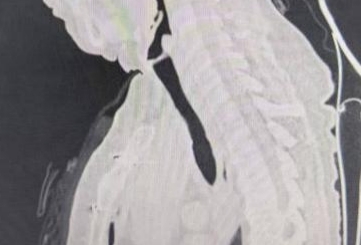

术前

原发性气管肿瘤是指原发于第一气管环以下至隆突以上范围内的气管肿瘤、多起源于气管后壁的膜部与软骨交界处的黏膜上皮和腺体,为呼吸系统的少见病症。成人主气管平均长度12cm,一般手术切除一期吻合最大长度不超过5cm。该患者主气管长度仅10cm,术中切除气管长度4cm,上、下切缘各2mm,切除总长度达4.4cm,近主气管一半长度,术中配合双侧肺门松解最大限度保证气管切除长度、最大限度降低气管吻合口张力,术后未进行下颌前胸减张缝合,大大提高患者术后舒适感加速患者康复。